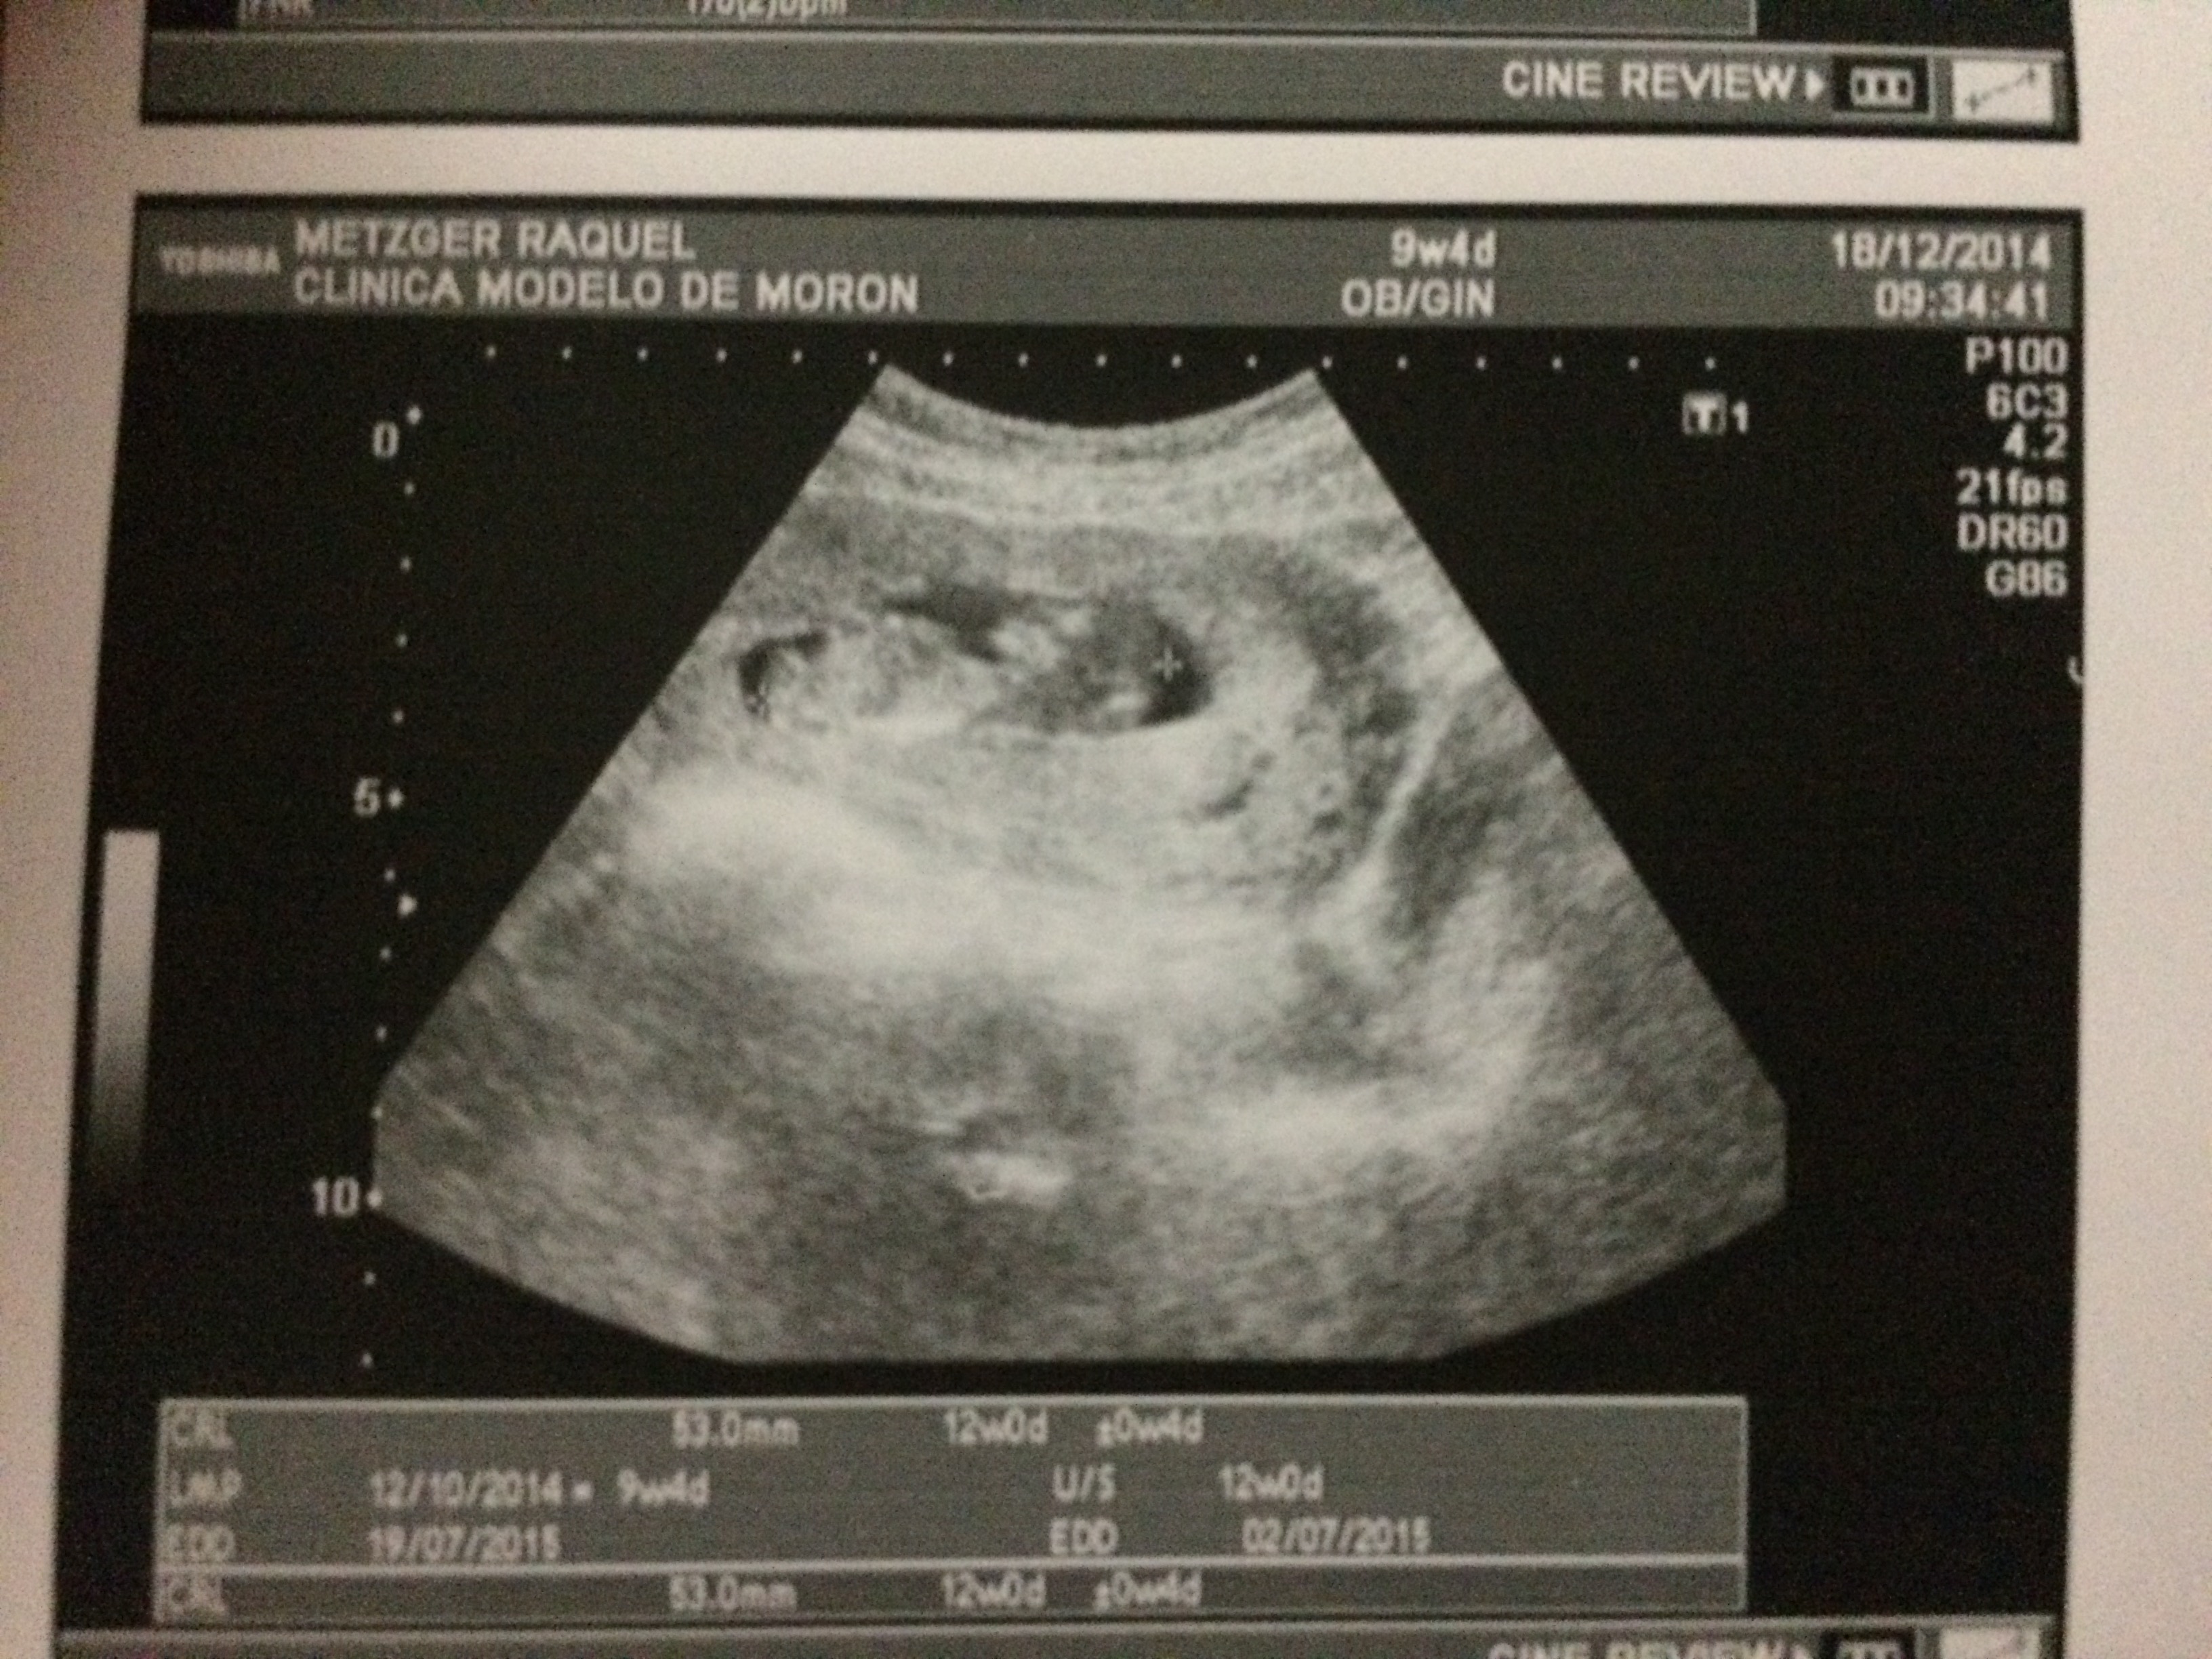

Many times God throws new things into our lives to change things up. We had one of these blessings made known to us in November, when we found out we will be welcoming a new baby to our family around July 2nd, 2015! We were pleasantly surprised, and thus began the search for a good doctor and hospital to have the baby in. It is something we take for granted in the United States, but the process here is much harder. So, we believe we found the correct clinic to go to and are now under the care of an Argentine Obstetrition here. Please pray that the pregnancy will progress well, and that baby Metzger will arrive safe and healthy.